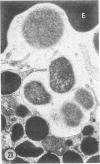

The prevalence of mast cells infiltrating bone marrow of different rats varied widely, as did the staining properties and size of their cytoplasmic granules. Bone marrow mast cells from several rats revealed large membrane-limited inclusions which stained metachromatically or orthochromatically and resembled inclusions in some macrophages. Ultrastructurally, mast cells varied widely in content of uniform dense granules or enlarged granules with less dense, fine grained content. Some of the large inclusions observed ultrastructurally in mast cells were heterophagic vacuoles which contained erythrocytes or reticulocytes, or remnants from other phagocytized cells, possibly neutrophils or unidentified homogeneous material. Smaller bodies, interpreted as fragments of erythrocytes, lay extracellularly near mast cells and occupied small, membrane-limited, heterophagic vacuoles in some mast cells. In other mast cells, communal vacuoles enclosed several specific cytoplasmic granules in various stages of disruption. The communal vacuoles occasionally opened to the extracellular space. A few large indeterminate vacuoles in mast cells contained amorphous flocculent matter which apparently derived either from coalescence of cytoplasmic granules through fusion of granule membranes or from endocytosis.